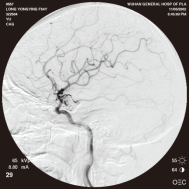

弹簧圈栓塞后造影示左椎动脉夹层动脉瘤消失, 左椎动脉、 多发动脉瘤夹闭术前、术中

左侧小脑后下动脉循环通畅